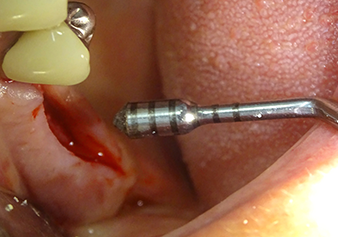

Lo strumento I2A (diametro 2,0 mm) è stato quindi impiegato per perforare il pavimento sinusale in modo graduale e su superfici molto ridotte. Tale metodo piezochirurgico previene il danneggiamento della membrana di Schneider. Durante l'utilizzo di Z25P, la membrana risultava già essere leggermente sollevata dal fluido di raffreddamento fornito attraverso la punta dello strumento (Fig. 3). La quantità di fluido di raffreddamento presente era solo del 50% per evitare che la sede dell'impianto registrasse un'elevata pressione.

La membrana di Schneider viene accuratamente scollata usando lo strumento Z25P (fase 1)

Fig.3: dopo la marcatura della posizione dell'impianto e l'espansione della sede, la membrana di Schneider viene accuratamente scollata usando lo strumento Z25P (fase 1).